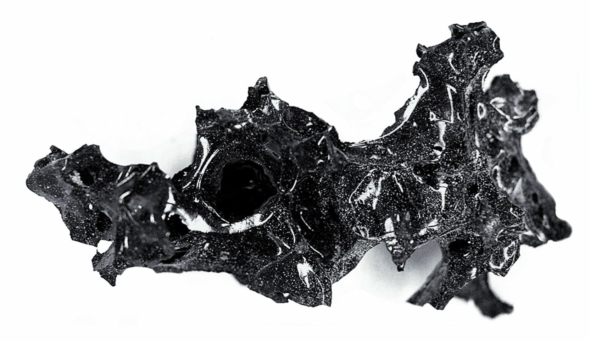

Il professor Petrone ha spiegato a Repubblica come sia avvenuta la sua scoperta: «Mi sono accorto che qualcosa brillava nella cenere, tra i resti del cranio esploso. Erano frammenti vitrei di colore nero, come ossidiana, ma molto friabili. Abbiamo subito prelevato alcuni campioni e l’analisi proteomica ha evidenziato acidi grassi, trigliceridi e capelli umani. Non poteva essere altro che il cervello».

Assieme alla sua équipe, ha provveduto a mandare i risultati al New England Journal of Medicine, la prestigiosa rivista americana, leader a livello mondiale, che ha voluto però alcuni approfondimenti per verificare la notizia senza possibilità di errori. «Abbiamo fatto altre analisi e abbiamo trovato sette proteine altamente rappresentate nel tessuto del cervello umano». Gli studi antropologici e le ricerche sul territorio hanno già portato a risultati eccezionali, fornendo importanti informazioni sullo stato di salute e sugli stili di vita delle vittime. L’altezza media era di circa 1 metro e 60 per gli uomini e 1,50 per le donne, ed erano generalmente sani, anche se qualcuno soffriva di artrosi ed ernie. Un’alta percentuale degli scheletri ritrovati mostra segni di un duro e stressante lavoro. La loro dieta era di cereali e legumi, arricchita da un certo numero di elementi base, come uva, fichi, mele, miglio, uova, patelle, vongole e ricci di mare. Facevano grande uso di frutta, visto che ne sono state trovate tracce di almeno cento tipi diversi. Per insaporire i pasti usavano pepe nero, aneto, finocchio, coriandolo, sedano, menta, papavero e lino. Ma siamo solo agli inizi della conoscenza di quel mondo lontano. Gli studi di antropologia fisica sono ora supportati da analisi di laboratorio sempre più sofisticate, associate a innovative ricerche sul Dna, che potranno chiarire persino origini e grado di parentela delle vittime. Come se la morte rivelasse molti più segreti della vita.